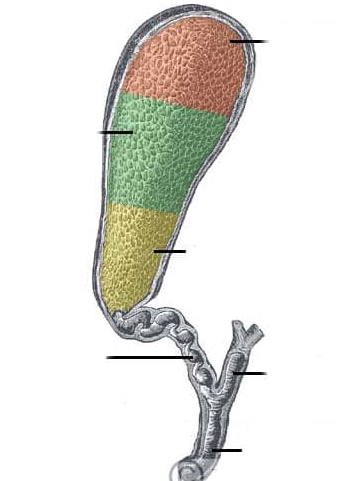

Fundus of gallbladder

orange highlight

Body of gallbladder

green highlight

Neck of gallbladder

yellow highlight

Cystic duct

pink highlight

Left hepatic ducts

Right hepatic ducts

Common hepatic duct

Common bile duct

Duodenal papilla within duodenum